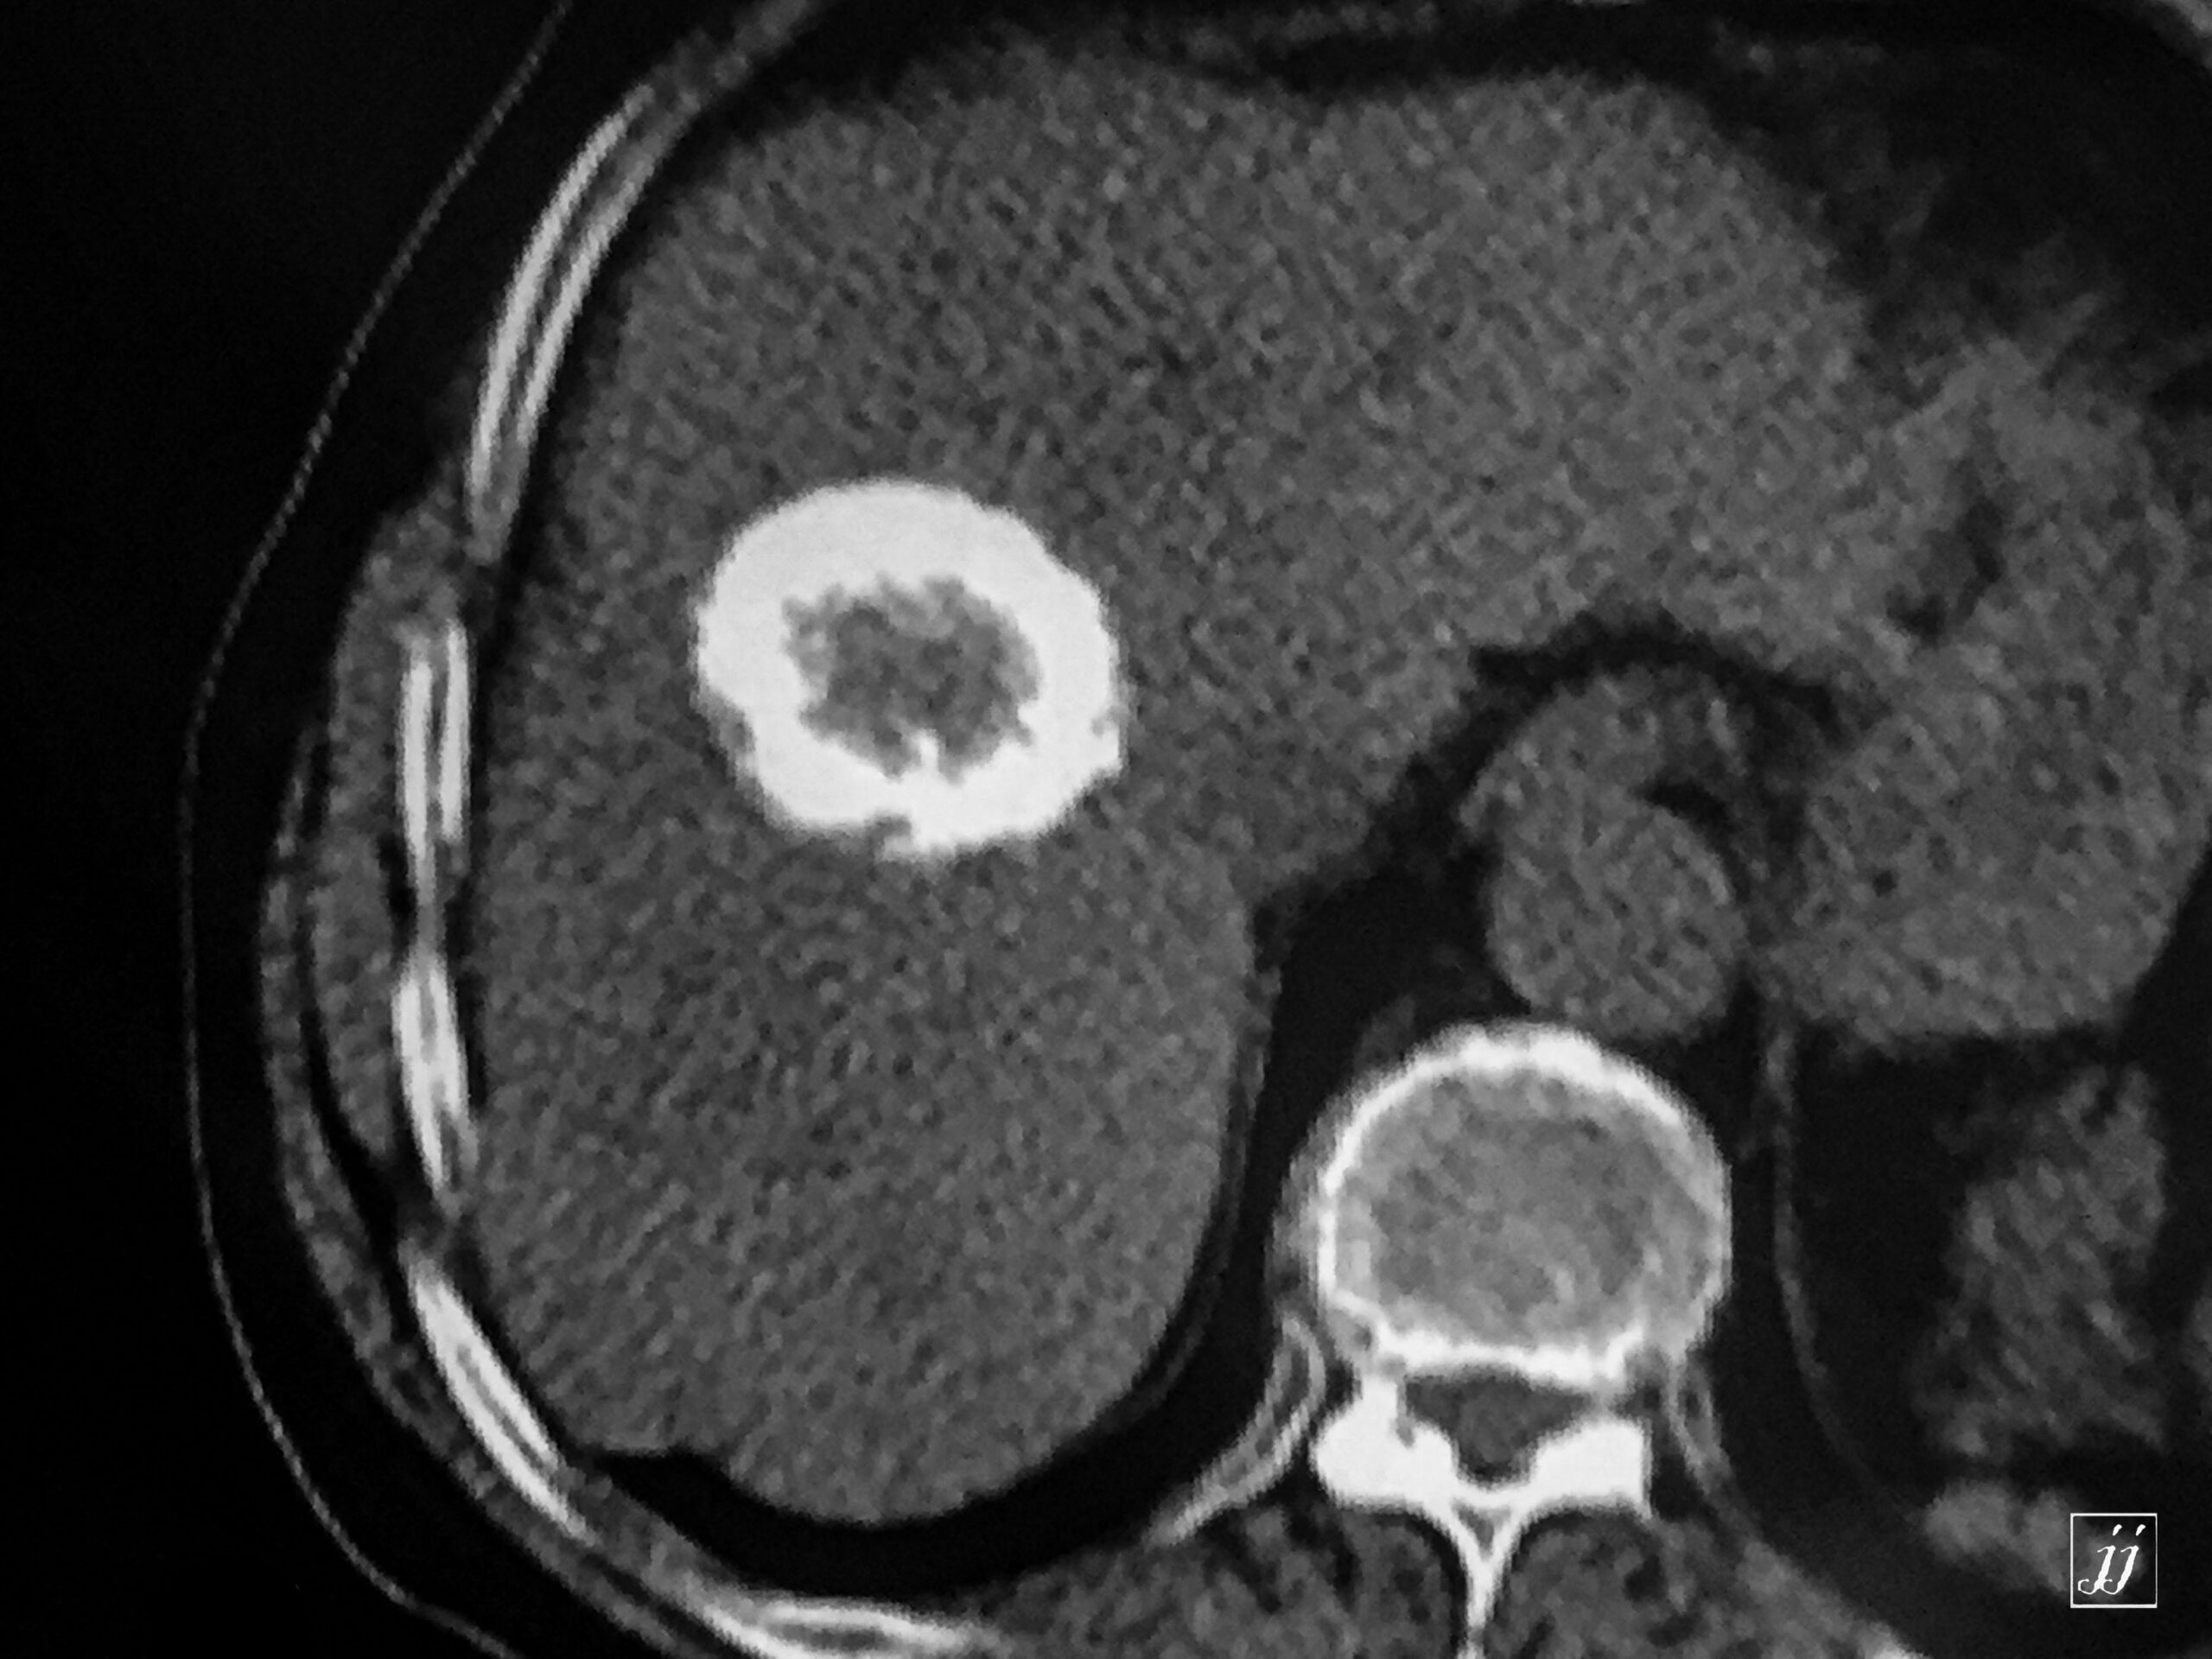

Abdomen- calcified hydatid cyst of the liver (4)